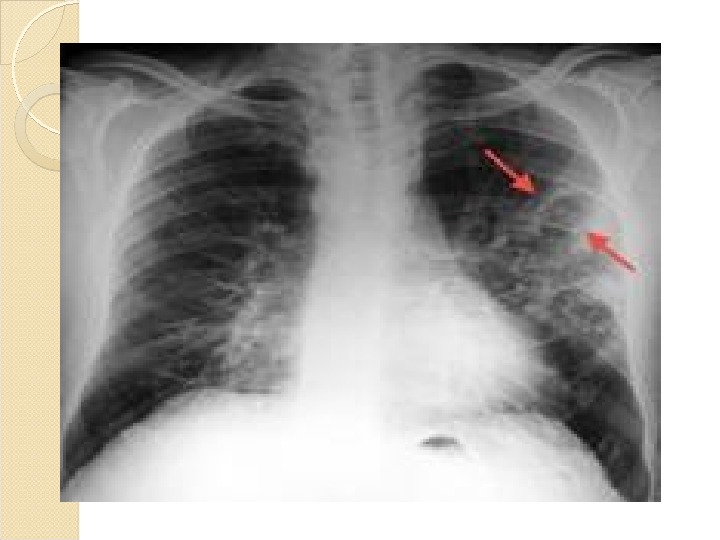

:max_bytes(150000):strip_icc()/iStock_000030303806_Large-56569fb83df78c6ddf291beb.jpg)